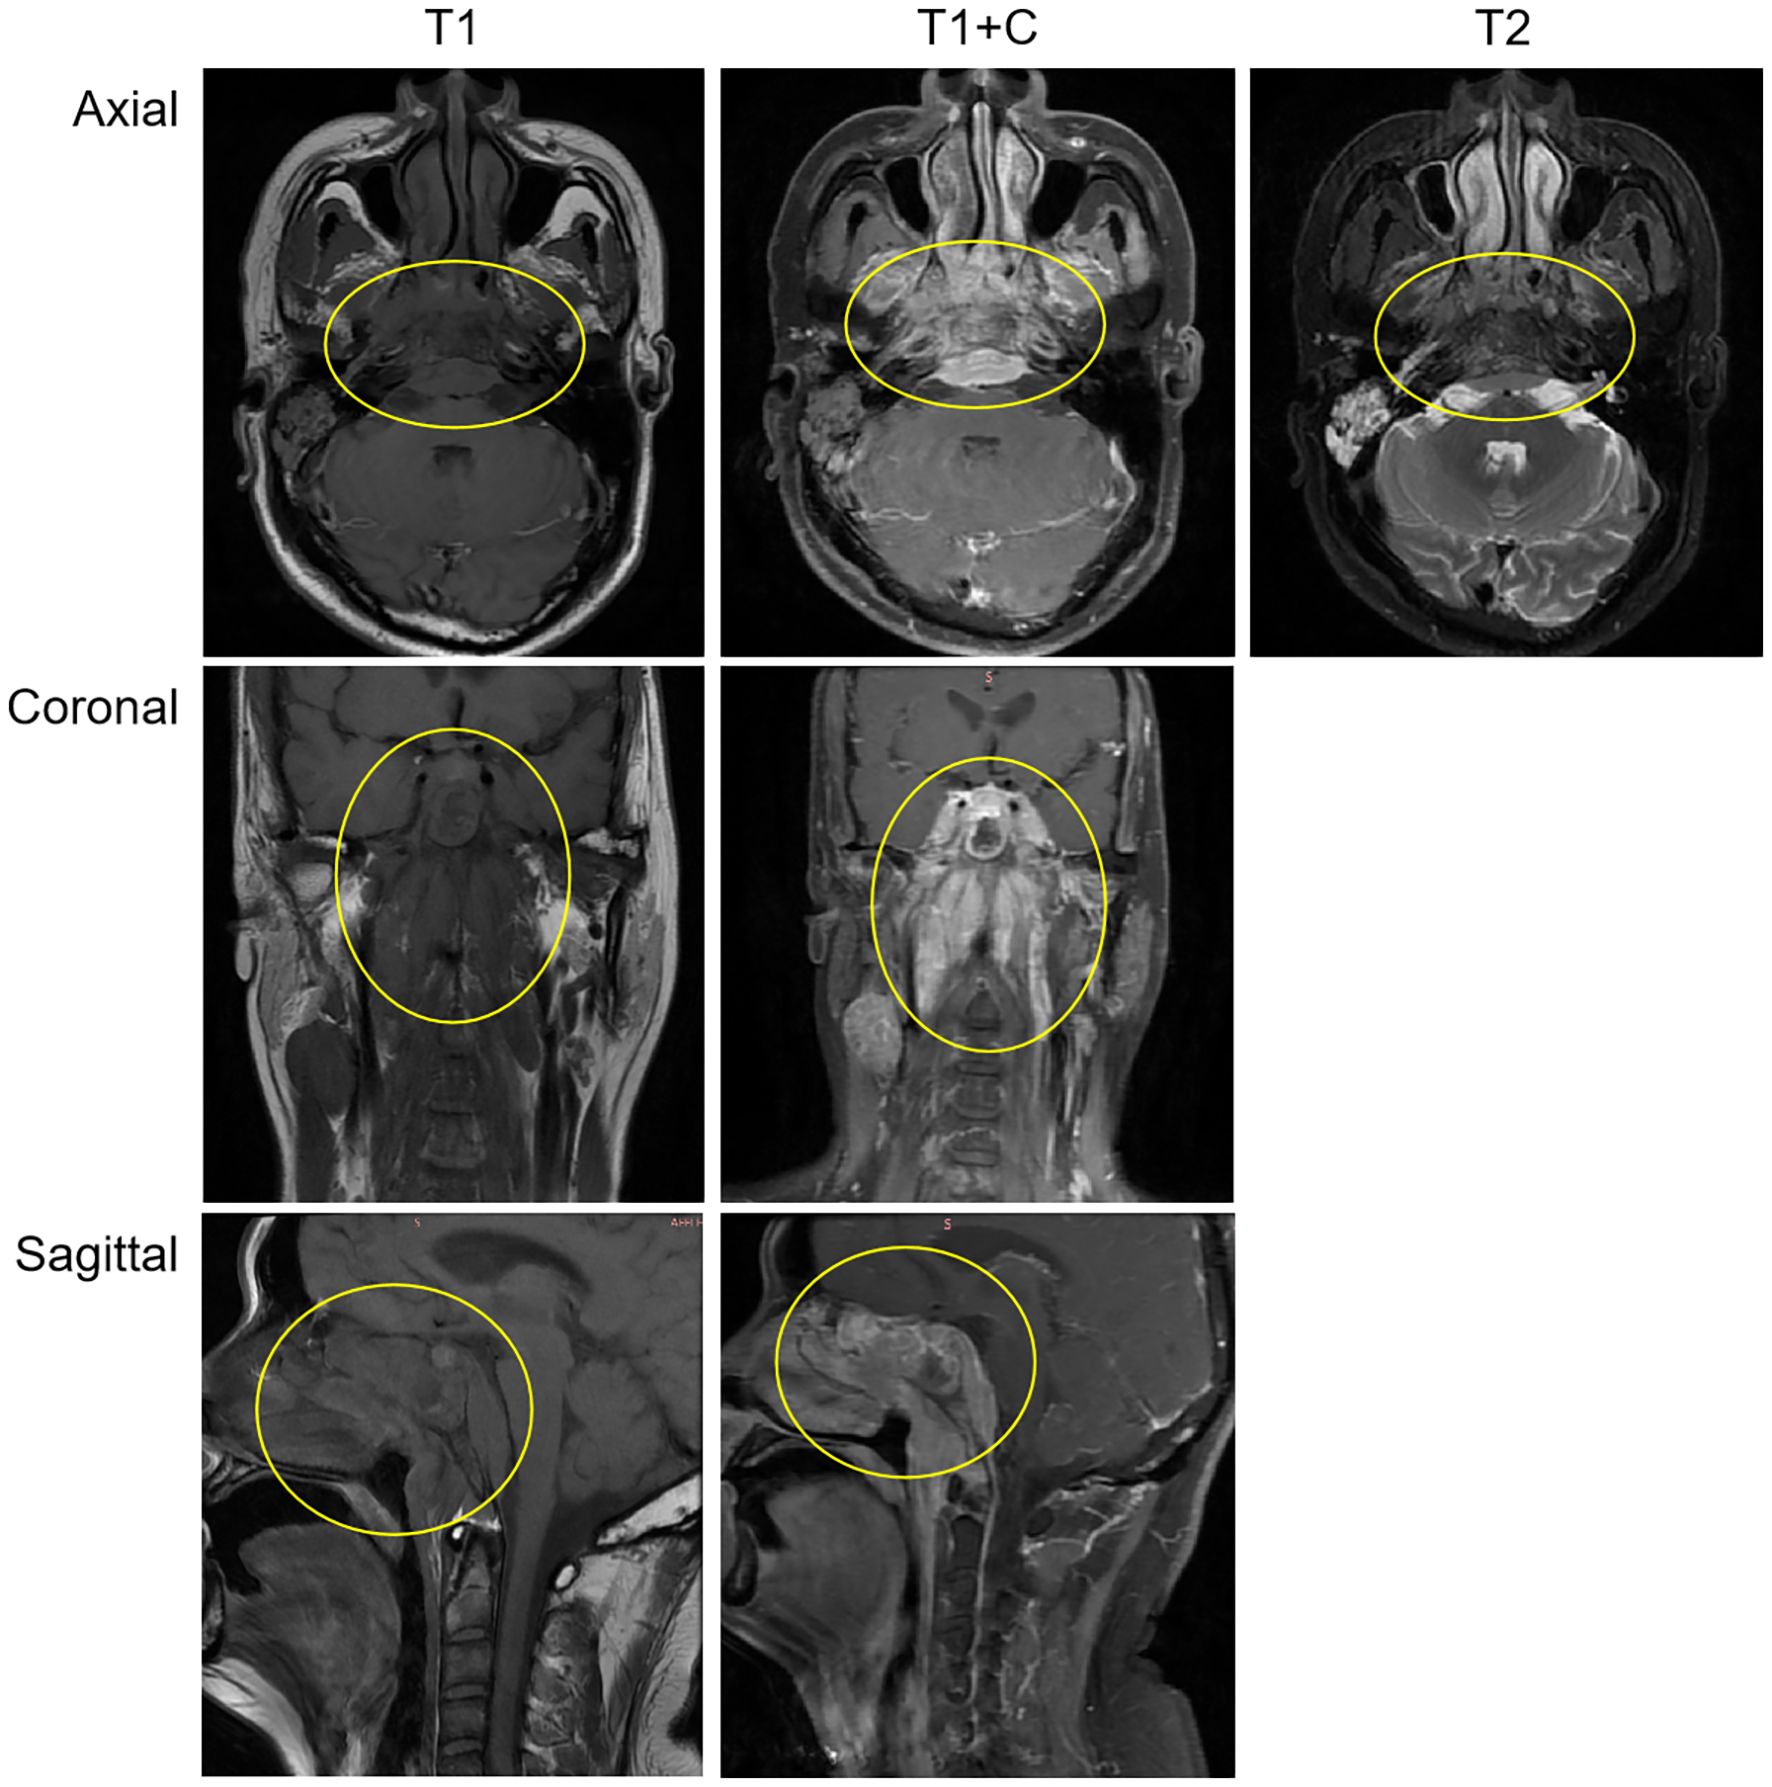

After admission, relevant auxiliary examinations were carried out. Serum tests on March 19, 2024 revealed an elevated cytokeratin 19 fragment (35.600 ng/mL). An EBV-DNA test (whole blood) was performed on March 20 (< 500 copies/mL). Nasopharyngeal and cervical magnetic resonance imaging (MRI) findings from March 20 indicated nasopharyngeal carcinoma with multiple lymph node metastases (Figure 1). The MRI demonstrated mucosal thickening in the nasopharyngeal roof and posterior wall with involvement of the lateral pharyngeal recesses. A soft tissue mass measuring 38 mm×20 mm in the largest axial dimension was identified, which showed isointensity signal on T1 WI and slightly hyperintense signal on T2W with significant enhancement after contrast enhanced scan. Obliteration of the bilateral pharyngeal recesses and eustachian tube orifices was observed. The lesion demonstrated extensive local invasion with encroachment into the parapharyngeal space, pharyngobasilar fascia, etc. Multiple enlarged lymph nodes ranging from small to large were identified in the retropharyngeal space and bilateral cervical levels II; through III and Va, some of which merged into masses. The dominant lymph node, located in the right level III, measured 26 mm×27 mm×35 mm in maximal dimensions. Positron emission tomography-computed tomography (PET-CT) demonstrated a standardized uptake value maximum (SUVmax) of 8.76 in the nasopharyngeal soft tissue mass, with SUVmax values of 7.52 in the bilateral parapharyngeal and cervical lymph nodes and 4.86 in the pulmonary nodule (Supplementary Figure 1).

Figure 1. The MRI demonstrated a soft tissue mass measuring 38 mm×20 mm in the largest axial dimension, which showed isointensity signal on T1 WI and slightly hyperintense signal on T2W with significant enhancement after contrast-enhanced scan. The mass involves the surrounding normal tissue. The findings suggest nasopharyngeal carcinoma; Multiple enlarged lymph nodes, of varying sizes, were observed in the retropharyngeal space and bilateral cervical regions, suggestive of metastatic involvement.